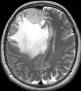

Machine learning has been widely adopted for medical image analysis in recent years given its promising performance in image segmentation and classification tasks. The success of machine learning, in particular supervised learning, depends on the availability of manually annotated datasets. For medical imaging applications, such annotated datasets are not easy to acquire, it takes a substantial amount of time and resource to curate an annotated medical image set. In this paper, we propose an efficient annotation framework for brain MR images that can suggest informative sample images for human experts to annotate. We evaluate the framework on two different brain image analysis tasks, namely brain tumour segmentation and whole brain segmentation. Experiments show that for brain tumour segmentation task on the BraTS 2019 dataset, training a segmentation model with only 7% suggestively annotated image samples can achieve a performance comparable to that of training on the full dataset. For whole brain segmentation on the MALC dataset, training with 42% suggestively annotated image samples can achieve a comparable performance to training on the full dataset. The proposed framework demonstrates a promising way to save manual annotation cost and improve data efficiency in medical imaging applications.

翻译:近年来,由于在图像分割和分类任务方面表现良好,医学图像分析广泛采用了机器学习。机器学习的成功,特别是监督学习的成功,取决于手动附加说明数据集的可用性。对于医疗成像应用来说,这种附加说明数据集不容易获得,需要大量的时间和资源来翻译附加说明的医学成像集。在本文件中,我们建议为大脑MR图像建立一个高效的注释框架,为人类专家提供信息性样图像,供人类专家作说明。我们评估了两种不同的大脑图像分析任务的框架,即脑肿瘤分割和整个大脑分割。实验显示,对于BRATS 2019数据集的脑肿瘤分割任务,培训一个只有7%的附加说明图像样本的分解模型,其性能与全数据集培训的性能相当。对于MALC数据集的整个大脑分割,用42%的附加说明性图像样本进行的培训,可以实现与全数据集培训的类似性能。拟议的框架展示了节省人工注解成本和提高医疗成像应用数据效率的有希望的方法。